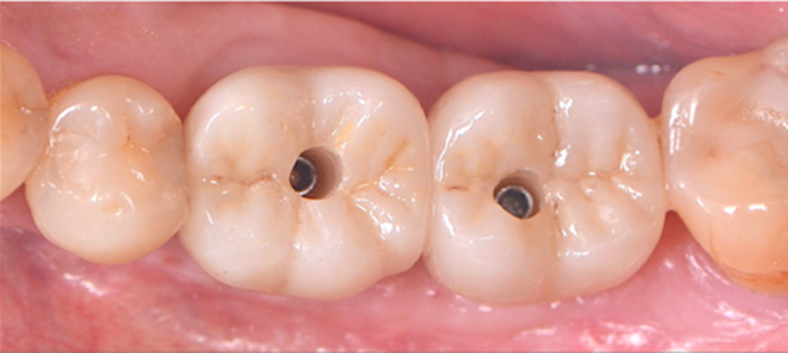

Selecionamos um caso clínico para ilustrar o fluxo de trabalho digital para Mini Cônico, onde foram planejadas duas coroas unidas nos elementos dentários 36 e 37 em zircônia monolítica, feitas sobre o pilar para próteses múltiplas.

Neste caso, a prótese múltipla foi desenhada sobre o Mini Cônico e as duas coroas foram fresadas unidas. Após a maquiagem final da zircônia monolítica, as coroas foram parafusadas sobre o Mini Cônico com um torque de 10 Ncm.

Podemos acompanhar o passo a passo das etapas, desde a seleção da altura do transmucoso do Mini Cônico até a instalação das coroas unidas no fluxo totalmente digital sem a utilização de componentes metálicos.